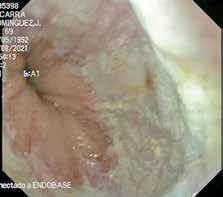

Ante la persistencia de la bradipsiquia y la dificultad para ejecutar órde nes moderadamente complejas, a pesar de que la madre decía que no veía grandes diferencias con respecto a su estado basal, se solicitó una resonan cia magnética cerebral. En la resonancia magnética se observó una altera ción de la intensidad de la señal en la porción central del cuerpo calloso, en concreto en esplenio y rodilla, con hiperintensidad en T2, hipointensidad en T1 basal y moderada restricción de la difusión; hallazgos que eran com patibles con el Síndrome Marchiafava-Bignami (Figura 3).

Resonancia magnética. Secuencia T1 y T2. Cortes sagital y transversal. Estudio artefactado por el movimiento del paciente. Estudio T1 donde se aprecia una lesión hipointensa con moderada restricción a la difusión en las capas medias del esplenio del cuerpo calloso, que en la secuencia T2 corresponde con una lesión hipertensa. Esta lesión en dicha localización y en el contexto clínico del paciente es altamente sugestiva de Marchiafava-Bignami.